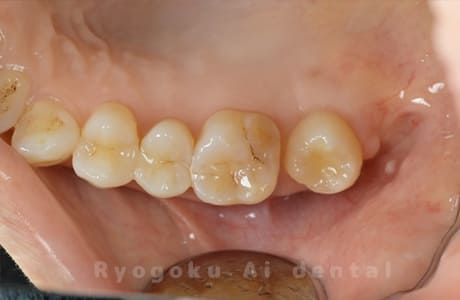

Case27

-

重度カリエス

歯牙移植咬合面術前 -

移植する親知らず

歯牙移植術直後咬合面

歯牙移植術後咬合面

歯牙移植術前側面

歯牙移植術中側面

歯牙移植術後側面

- 原因

- 重度カリエス

- 治療内容

- 自家歯牙移植、部分矯正

- 治療費用

- 220,000円(移植費用)

110,000円(部分矯正費用)

虫歯が大きく、保存不可能となった歯を上の親知らずと交換する自家歯牙移植を行いました。移植歯が小ぶりであったため、部分矯正を行い問題なく噛み合い、経過良好です。